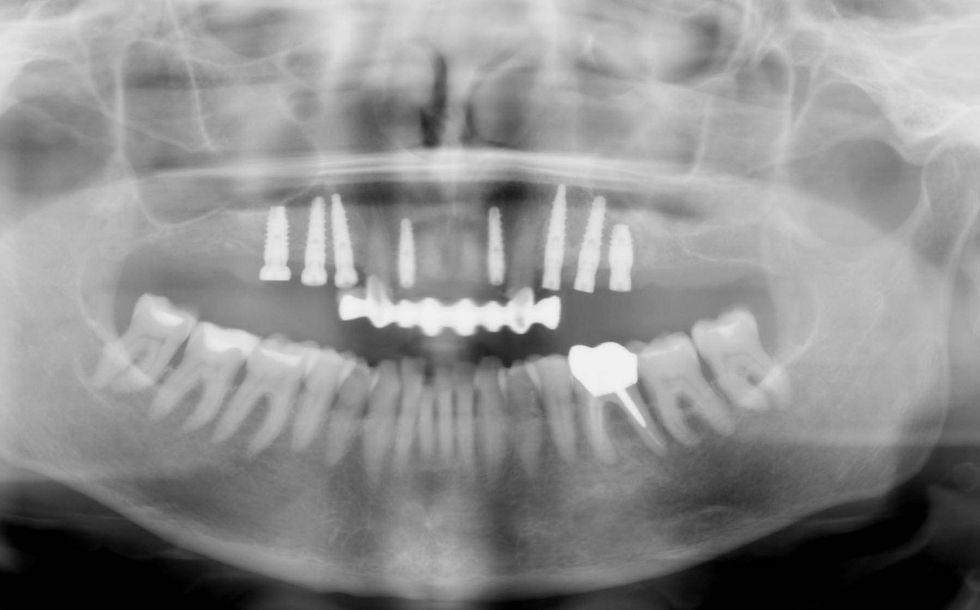

Initial orthopantomography. Superior teeth are all affected by severe periodontal disease, severe mobility, deep periodontal pockets, bleeding on probing, recurrent abscess and vestibular migration of the anterior dental sector, that make the prognosis of most of the teeth unfavorable.